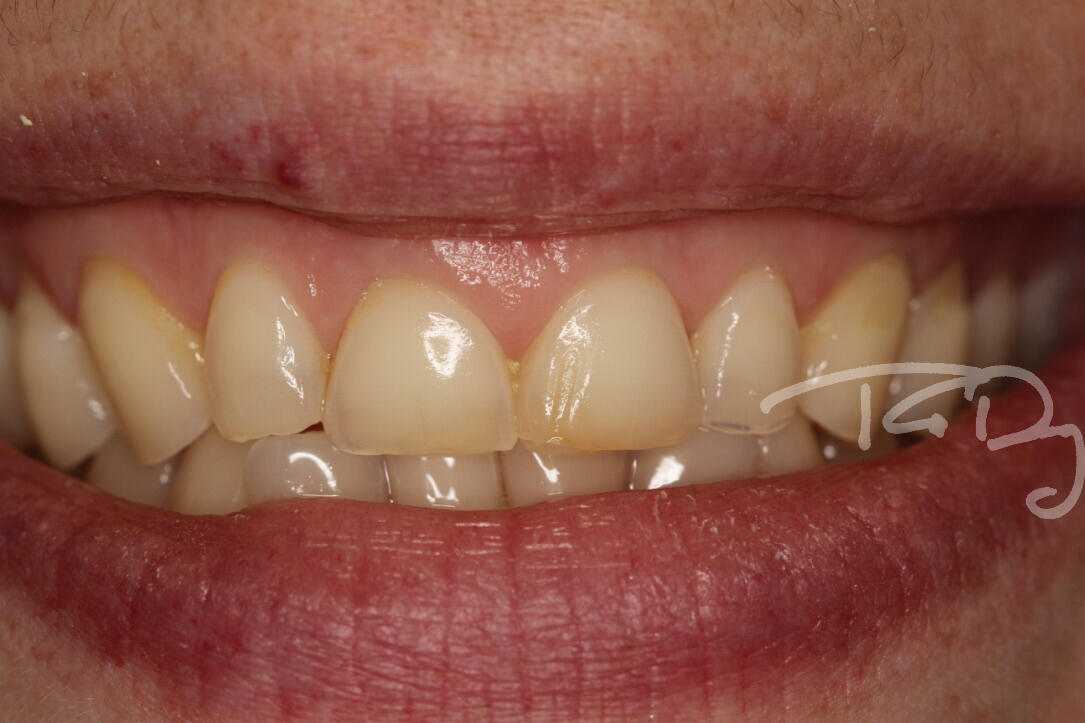

5 Review AppointmentA week later I will see you to make sure you are completely happy.LongevityTreatments on these upper teeth were done to protect them after heavy, longterm erosion.Thomas protected the teeth with beautifully strong glass ceramic crowns (shown below) after using the Dahl technique.Immediately after they were completed they were brighter, provided a better bite and better filled the gaps to support the shape of the gums.Even two years later, the above photo shows that gum health is excellent and the crowns are showing no wear.

Treatments on these upper teeth were done to protect them after heavy, longterm erosion.Thomas protected the teeth with beautifully strong glass ceramic crowns (shown below) after using the Dahl technique.

Immediately after they were completed they were brighter, provided a better bite and better filled the gaps to support the shape of the gums.

Even two years later, the above photo shows that gum health is excellent and the crowns are showing no wear.The patient is extremely happy with the outcome. Read more about how Intelligent Smile Design works to protect teeth and let you put your best smile forward.